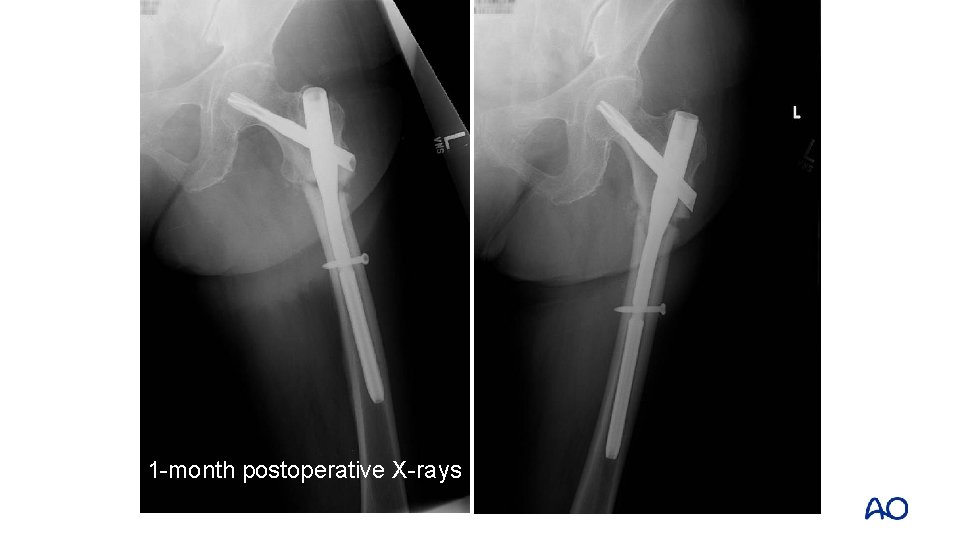

1 -month postoperative X-rays

Comments • Varus reduction • Minimal healing at fracture site